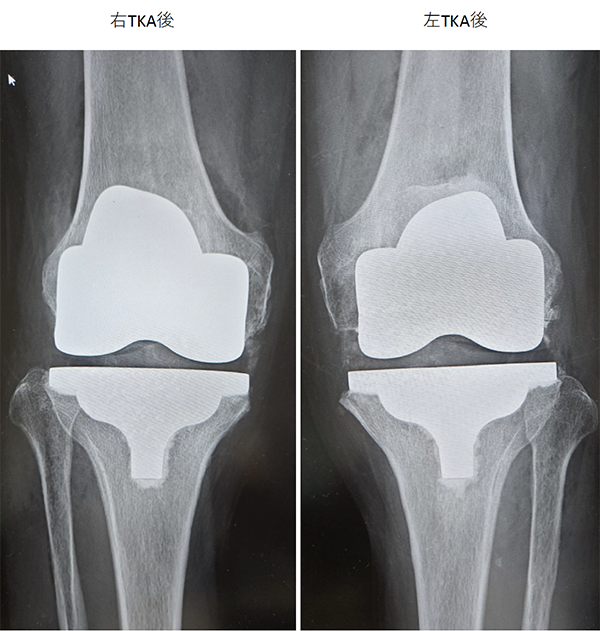

当院にて人工ひざ関節全置換術(TKA)を施行。両側の手術を同時に行いました。両側同時手術の場合でも入院期間は片側手術の場合と大きく変わらず(プラス1週間程度)、麻酔も1回で済むために身体的、経済的な負担の軽減を期待できます。また両ひざが同程度に悪いケースも少なくなく、同時に行うことで左右のバランスが良くなるためにリハビリをスムーズに進めることが可能となります。

〈手術前のレントゲン〉

〈手術後のレントゲン〉(正面・側面)

右膝

左膝